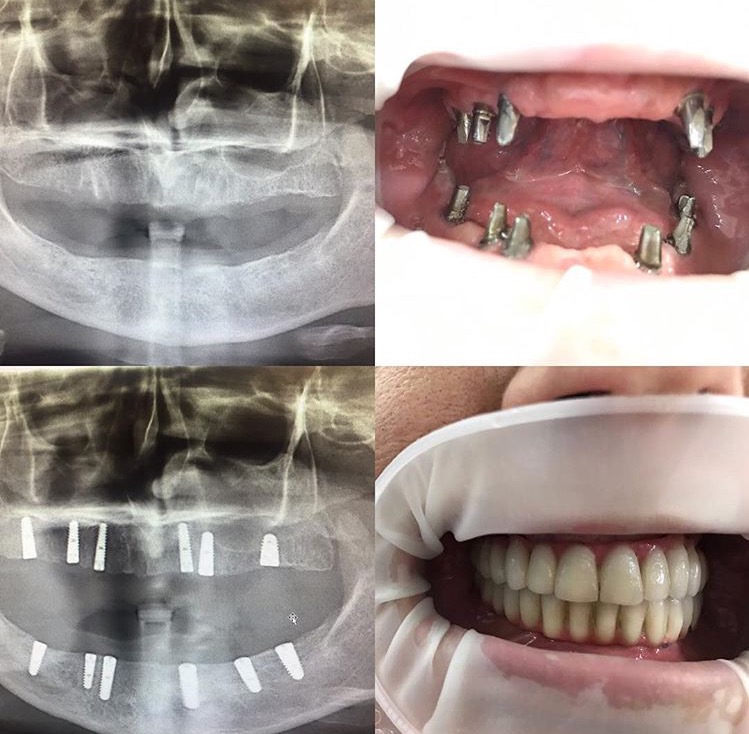

Tansel Hamza

Diş Estetiği ve İmplant (Bölüm 2)